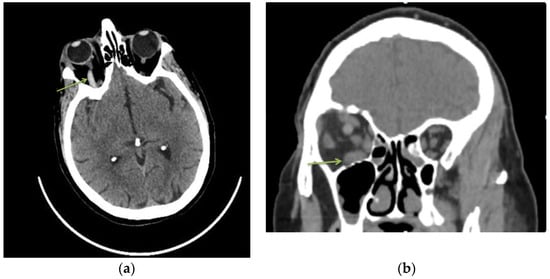

Superior ophthalmic vein thrombosis is a rare pathology in current practice with a multifactorial etiology [2]. Clinically, symptoms are often acute, with eye pain, chemosis, ptosis, conjunctival congestion and decreased visual acuity [6]. In these cases, risk factors can be local or systemic but usually include at least one component of the Virchow triad (hypercoagulability, hemodynamic changes (stasis, turbulence), endothelial injury/dysfunction) [7]. The diagnosis is usually based on CT or MRI results and according to the patient’s symptoms. In our case, CT scan revealed a hyperreflectivity at the level of the right ophthalmic vein and inferior rectus muscle hypertrophy (Figure 1).

Figure 1.

A 77-year-old woman, with hypertensive pathology, presented to the emergency department complaining of eye ptosis, chemosis and conjunctival congestion. The patient was known to have high myopia (both eyes) and amblyopia (LE). The ophthalmological examination revealed best-corrected visual acuity (BCVA) on the right eye 0.5 and 0.06 for left eye. Intraocular pressure (IOP) was 25 mmHg in RE and 14 mmHg in LE. The anterior segment of the left eye was normal. In the RE we noticed diffuse conjunctival congestion, chemosis and eyelid ptosis. Ocular movements were normal in both eyes. Pupillary light reflex was bilaterally intact. Hertel’s exophthalmometry revealed a proptosis of 20 mm in the right eye vs. 17 mm in the left eye. Non-contrast computed tomography (CT) of the brain and orbits revealed a hyperreflectivity at the level of the right ophthalmic vein (a) and inferior rectus muscle hypertrophy (b). Routine biochemical examination showed an increase of inflammatory markers (C-reactive protein, fibrinogen) and a high D-dimers value. Blood culture and a bacteriological conjunctival exam were negative. Additionally, other secondary causes were excluded (tumors, autoimmune diseases, infections). (a) Axial sections of non-contrast head CT scan—hyperreflectivity of the right ophthalmic vein. (b) Non-contrast head CT coronal scan—inferior rectus muscle hypertrophy.